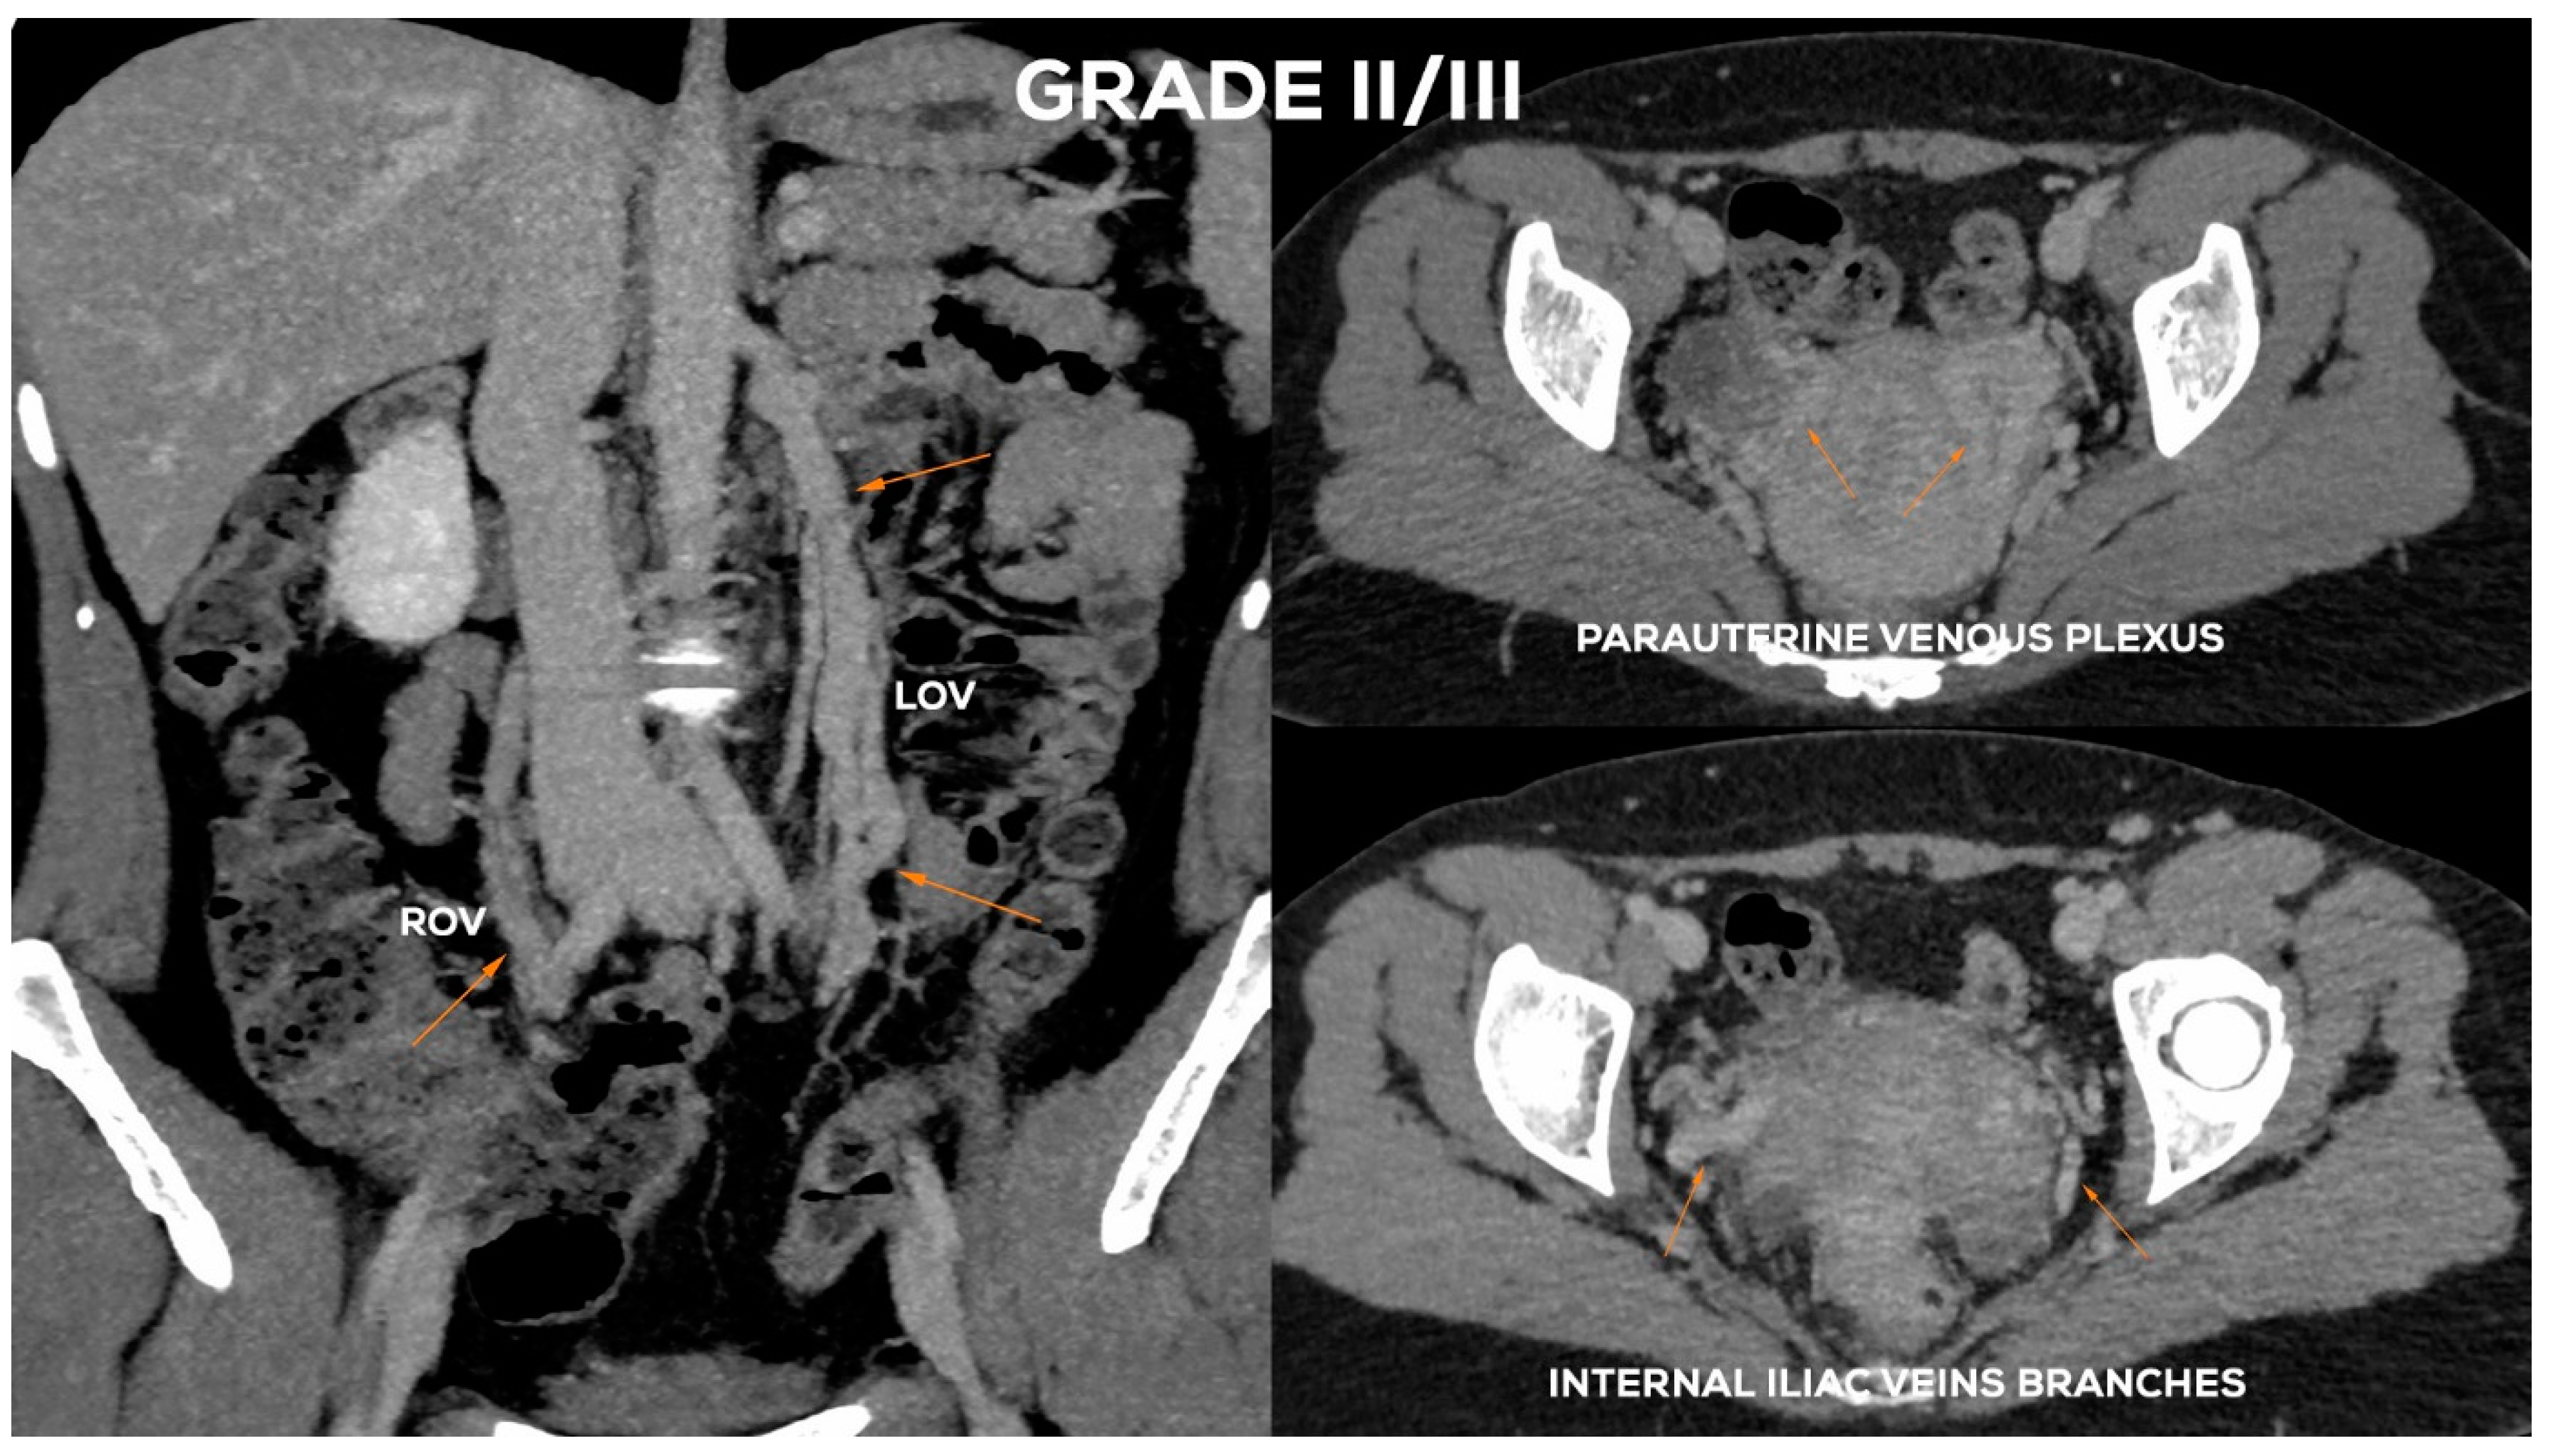

4.2.4. Grade II/III (GII/III)

In the Grade II/III (Figure 11), the LOV trunk shows a clear insufficiency with dilatation up to 7.5–8 mm. Grade II/III distension of the left para-uterine venous plexuses is significant, usually up to 7 mm. The LIILV runoff is also dilated. Often the uterine vein or another branch of the LIILV (bLIILV) drainage becomes wider, even up to 6.5–7 mm. With GII/III insufficiency, there is a gradual volumetric overload of the right side with the distension of the lower ROV segment (ØROV up to 5.5–6 mm). The lower part of ROV when evaluated during the Valsalva maneuver or in a sitting position shows venous reflux. The middle and upper segment of the ROV is still efficient, although usually moderately widened. The venous plexuses of the right para-uterine region continue to distend (rPUV up to 6–6.5 mm). RIILV runoff (bRIILV up to 6 mm) is overloaded (Figure 13).

Figure 13.

Typical findings in patient with Grade II/III ovarian veins insufficiency seen on CTV images in coronal and axial planes.